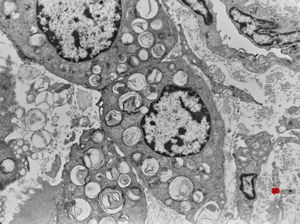

F, 2m. | surfactant deficiency